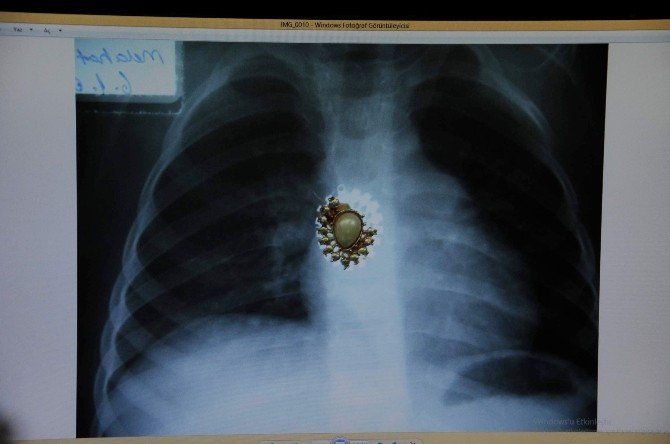

Koleksiyonda çıkan cisimlerden bilgiler veren Prof. Dr. Melikoğulları, "Yemek borusu içinde çocuklardan, iğne, kalemtıraş çıkarıyoruz. Sol akciğer bronşuna vida saplanan bir çocuk geç kalındığı için hayatını kaybetti. Soluk borusuna giden parça hastanın ileriki dönem için sakıncalıdır" ifadelerini kullandı.